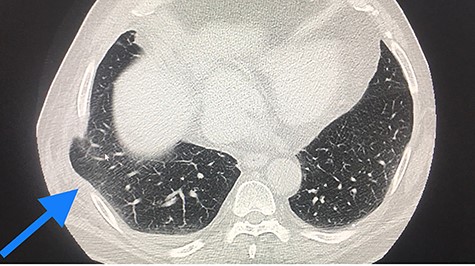

CT scan, lung herniation in the right hemithoracic, with clear position of the lung between the ribs and under the muscle straits.

Thoracic computed tomography (CT) scan showed a pulmonary hernia in the seventh intercostal space (ICS) due to a defect in the chest wall, minimal haematothorax, lung emphysema, but no pulmonary nodules and no skin or mediastinal emphysema (Fig. 2).